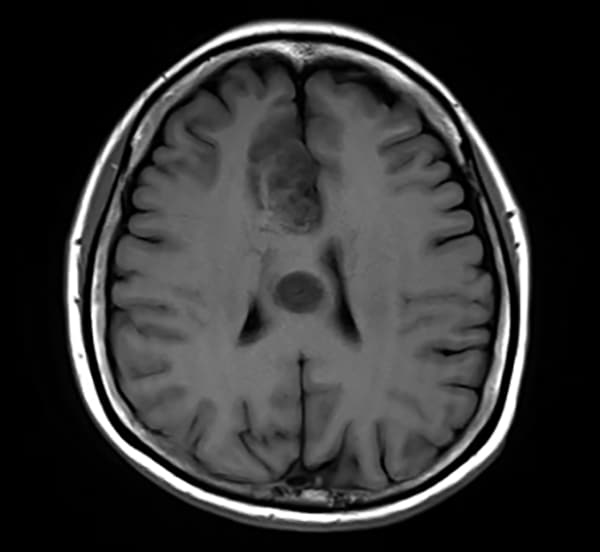

T1WI低信号、T2WI高信号、FLAIR高信号、DWIでやや高信号の腫瘤。Gdで腫瘤は造影されず、DSC-Perfusionでは辺縁~中心部に一部血流の高い部分あり。MRスペクトロスコピーではCho上昇とNAA低下がみられる。Low grade gliomaを疑う。後日、摘出手術が施行され、病理診断はoligodendroglioma NOS(Grade 2)であった。